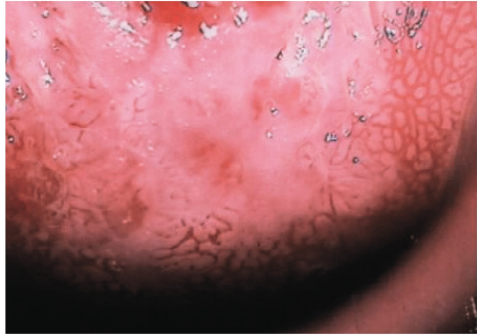

41 38 歳の女性。子宮頸部の細胞診で異常を指摘されたため来院した。初経 12 歳。 月経周期 28 日、整。内診で子宮は前傾前屈で正常大である。両側付属器は触知し ない。腟鏡診で分泌物は褐色少量である。コルポスコピィの写真別冊No. 6を別 に示す。 次に行う検査はどれか。 (A)骨盤部 MRI (B) 子宮内膜組織診 (C)血中 SCC 値測定 (D) 子宮頸部狙い組織診 (E)腟分泌物の細菌培養